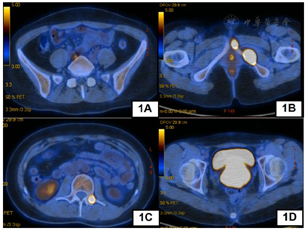

我院完善PET-CT提示宫颈FDG高代谢占位,较大截面约7.0 cm×6.0 cm,符合宫颈癌改变,伴阴道受累,请结合专科检查。右侧髂动脉后方FDG高代谢淋巴结,大小约1.2 cm×0.8 cm,转移可能大。腰2椎体左侧附件、左侧耻骨联合处及左侧耻骨下支转移瘤。子宫体形态欠规整,请结合相关检查(图1)。肿瘤标志物:CA125 46.57 U/ml,CA19-9 58.78 U/ml,SCC 0.5 ng/ml。结合患者妇科内诊及影像学检查综合考虑为宫颈癌,遂行超声阴道下经阴式宫颈肿物穿刺活检,病理提示(宫颈)考虑腺癌,组织少,建议术后免疫组化辅助诊断。